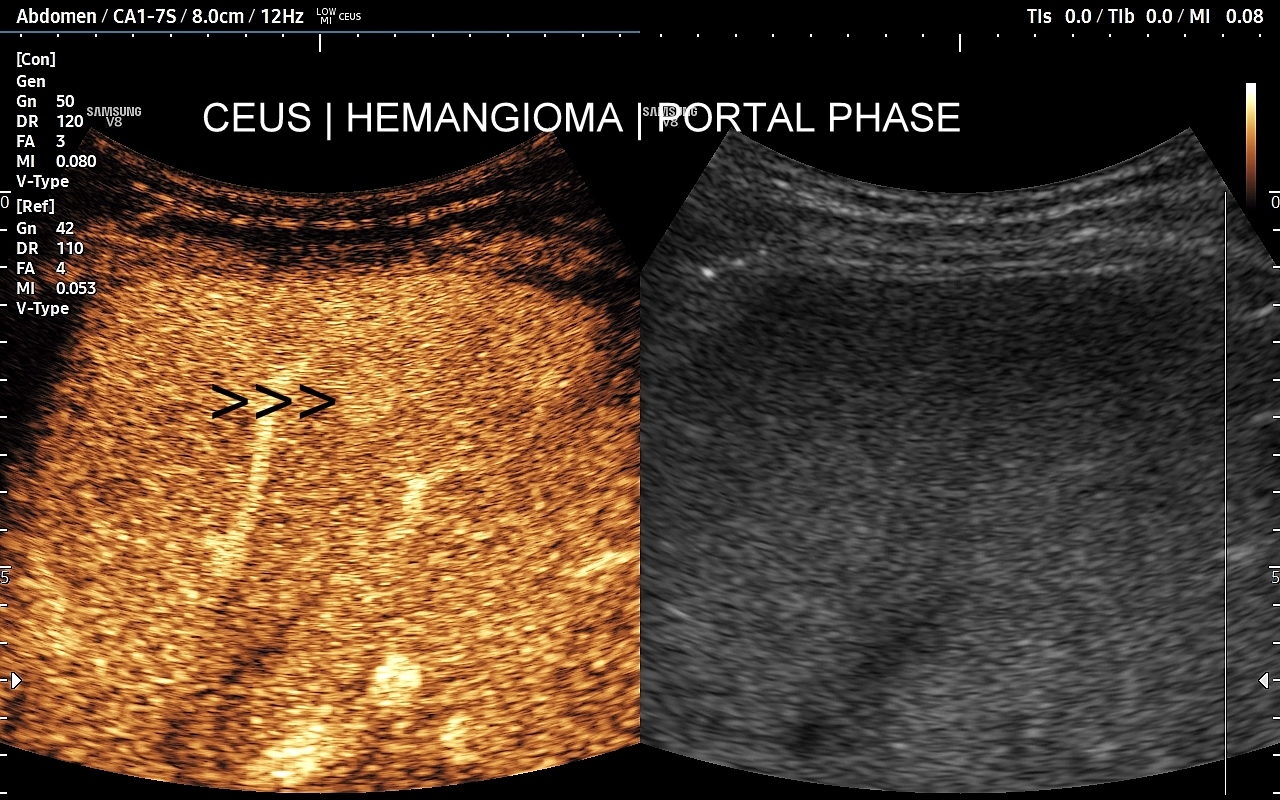

Najbardziej charakterystyczną cechą naczyniaka wątroby w badaniu CEUS jest jego wypełnianie w postaci guzkowej (ang. peripheral nodular enhancement) od obwodu ku centrum zmiany (ang. centripetal). Szybkość wypełniania bywa różnorodna, może być powolna lub szybka. W przypadku szybkiego wypełniania (tzw. flash-filling), w celu wykazania charakterystycznego centrypetalnego wypełniania niezbędna może być postprocessing’owa analiza poklatkowa zapisanego nagrania badania. W fazie późnej naczyniak wątroby pozostaje izowzmocniony lub hyperwzmocniony w stosunku do natywnego miąższu wątroby.

W przypadku dużych naczyniaków obszary, które uległy wykrzepianiu pozostają awaskularne przez wszystkie fazy badania CEUS, tj. nie wypełniają się kontrastem (nonenhancing). W przeciwieństwie do powyższego konstelacja, w której to w fazie wczesnej pojawia się wzmocnienie, a następnie w fazie wrotnej lub późnej ulega wypłukaniu (hypoenhancement) świadczy o cechach złośliwych diagnozowanej zmiany ogniskowej w wątrobie i wyklucza rozpoznanie naczyniaka.